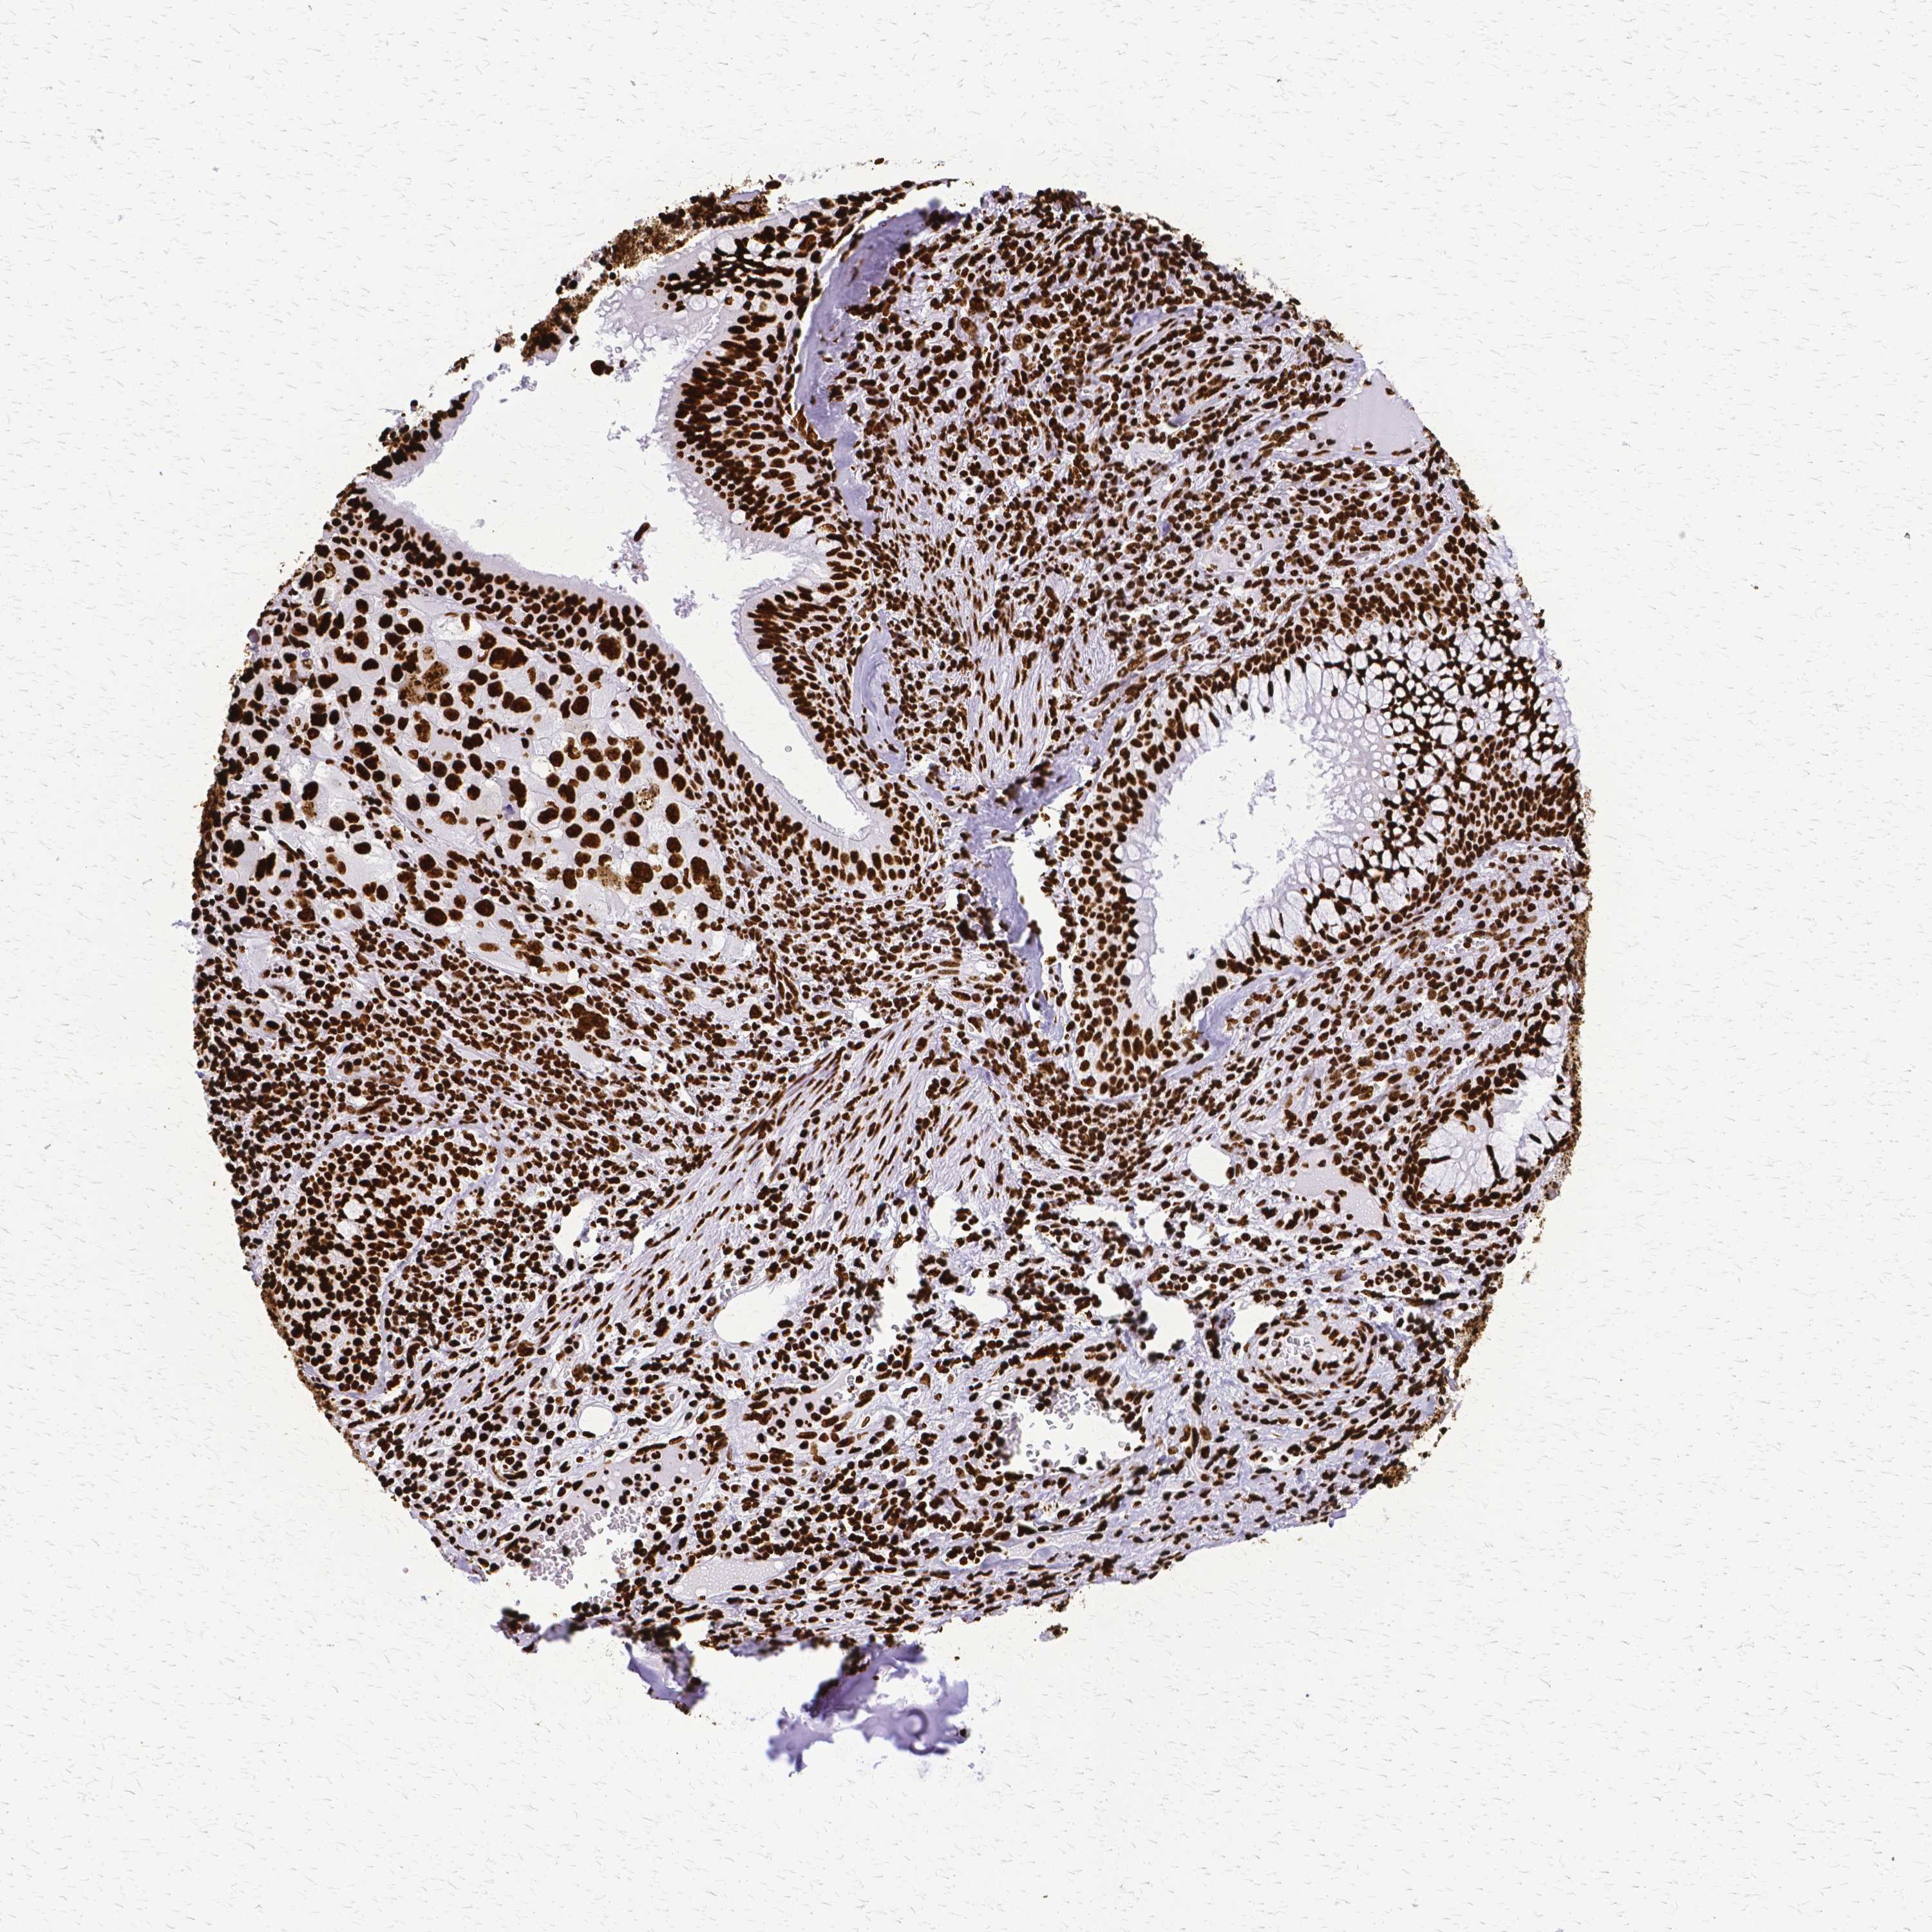

CANCER LUNG CANCER Show tissue menu

LUAD TCGA LUAD VALIDATION LUSC TCGA LUSC VALIDATION PROTEIN LUAD CPTAC PROTEIN LUSC CPTAC PROTEIN EXPRESSION

ANTIBODIES

AND

VALIDATION